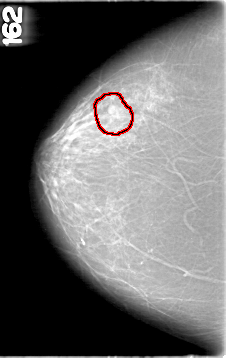

D_4094_1.RIGHT_MLO

RIGHT_CC LINES 5356 PIXELS_PER_LINE 3376 BITS_PER_PIXEL 12 RESOLUTION 43.5 OVERLAY

FILE: D_4094_1.RIGHT_MLO.OVERLAY

TOTAL_ABNORMALITIES 1

ABNORMALITY 1

LESION_TYPE MASS SHAPE ROUND MARGINS OBSCURED

ASSESSMENT 0

SUBTLETY 4

PATHOLOGY BENIGN

TOTAL_OUTLINES 1

BOUNDARY